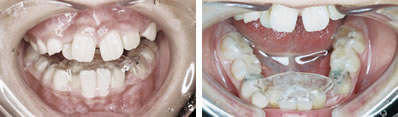

特別な装置を用いずに治療した例

パノラマレントゲンで前歯部分に過剰歯などの異常が無いことを確認。セファログラムレントゲンの分析から、左上の1番目の永久歯(中切歯)が内側に入っていることが問題であることを確認。

その後、木ヘラ(アイスの棒など)を用いて、歯を外側に出すトレーニングを行いました。